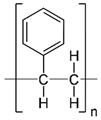

| Polymers | Structure | Fabrication Method | Commercial Products/Literatures | Comments | Reference |

|---|---|---|---|---|---|

| Polycarbonate (PC) |  | Ion-track etching | Estrogen | Excellent stability against oxidation and biodegradation and improves antifouling properties | [151] |

| Polyethylene (PE) |  | Ion-track etching | Catapress (Clonidine), Boehringer IngelheimClimara (Estradiol), Berlex | Physico-chemical stability andordered pore formation with superior membrane performance | [152] |

| Polyethylene terephthalate (PET) |  | Lithography | Ketoprofen | Biostable, antifouling, has better performance of membranes, in useful in preparing surgical meshes and ligaments | [153] |

| Polystyrene (PS) |  | Lithography | d-limonene, ibuprofen | Chemical resistance, easy processing, lower cost, exhibits enhancements in strength, stiffness, toughness, and ductility | [154] |

| PC, PE | - | Ion-track etching | Estraderm (Nitroglycerin), Rotta Research | Cost-effective and biocompatibility is fairly good | [155] |

| PC, PE, PET, PS | - | Phase separation | Deponit (Nitroglycerin), Pharma SchwarzHabitrol (Nicotine), Novartis | Cost-effective and biocompatibility is fairly good | [154,156] |

| Polyurethane (PU) |  | Sol-gel/solvent casting | Vivelle (Estradiol), Novartis | Good elasticity, biodegradable, suitable for hydrophilic drugs, biocompatibility is fairly good | [154] |

| Polysiloxane (silicone) |  | Sol-gel/solvent casting | Prostep (Nicotine), Lederle, Transderm Nitro (Nitroglycerin), AlzaSyncro-Mate-C (Norgestomet) | Better insulation, excellent biocompatibility, and fabricated easily for hydrophilic drugs | [157] |

| Polyisobutylene (PIB) |  | Solvent casting | Aminopyrene, Mitsubishi Petrochem Co., Japan | Good adhesive drug impermeable layer and high degree of tack or self-adhesion | [158] |

| Polymethyl methacrylate (PMMA), poly (2-hydroxy ethyl methacrylate) |  | Layer by layer deposition | Androderm (Testosterone), SmithKline Beecham | Physical strength and transparency | [159] |

| Polyvinyl alcohol (PVA), Poly (ethylene-co-vinyl acetate) |  | Solvent casting | Nitro-Dur I (Nitroglycerin), Key PharmaTestoderm TTS (Testosterone), Alza | Rate-controlling membranes, high membrane permeability, hydrophilicity and strength, suitable for lipophilic drugs | [160] |

| Polyacrylic acid, polyacrylate, polyacrylamide |  | Layer by layer deposition | Epinitril (Nitroglycerin), Rotta ResearchMonsanto (Fentanyl), Dow Corning | Good adhesivity and spreadability and contains a drug impermeable layer | [160] |

| Polylactides (PLA), polylactic-co-glycolic acid (PLGA), polyglycolides (PGA) |  , ,  | Sol-gel/solvent casting | Propranalol, Exxon Chemical Co. | Good biocompatibility; lactic and glycolic acids are the degradation products and they are easily eliminated from the body | [161,162] |

| Polyvinyl pyrrolidone (PVP), poly (N-vinyl pyrrolidone) |  | Sol-gel/solvent casting | Cytarabine, ara-ADA, Polyscience | Superior biocompatibility, has suspension capabilities, antinucleating agent, and enhances release rate | [163] |

| Polyethylene glycol (PEG) | Sol-gel/solvent casting | Miconozale, Rohm, Germany | Chemically inert and free of leachable impurities | [164] | |

| Oxide plus polymer | - | Sol-gel/solvent casting | Superior biocompatibility and has narrow pore size | ||

| Polymer coating on support membrane | - | Layer by layer deposition | [165] |